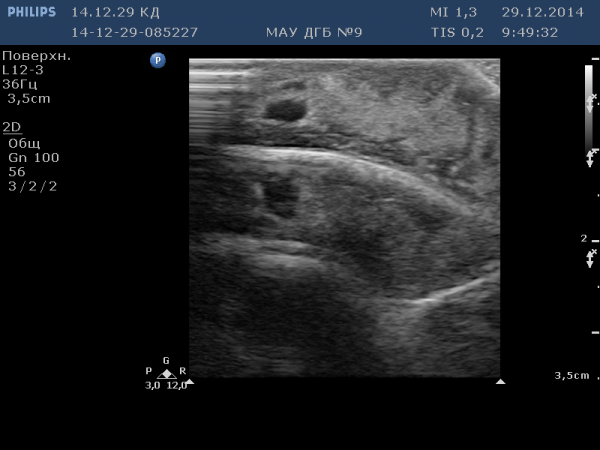

№1 - артефакт зеркального отражения. (пациент с гемангиомой мягких тканей волосистой части головы):